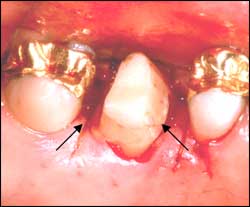

Gum repositioned to expose tooth preparation (arrows)